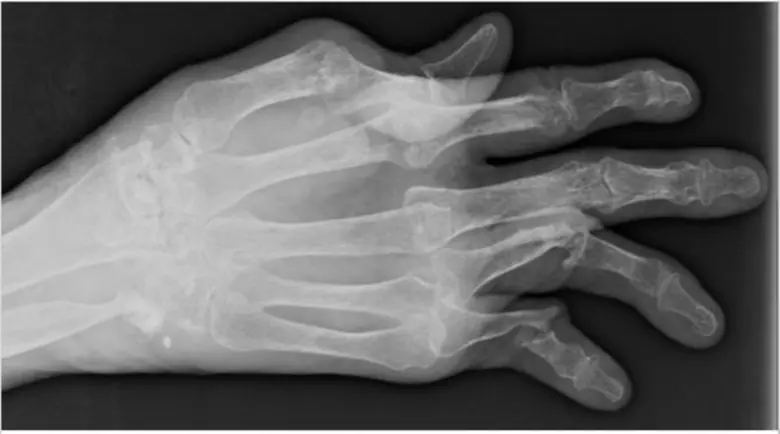

โรคสะเก็ดเงิน เป็นอาการอักเสบที่ส่งผลกระทบต่อผิวหนังและข้อต่อ โดยอาการที่พบบ่อยที่สุดคือผิวหนังแตกเป็นสะเก็ดและคัน แต่โรคนี้สามารถส่งผลกระทบรุนแรงยิ่งกว่านั้น สำหรับผู้ป่วยจำนวนมาก หนึ่งในความยากลำบากที่สุดในการอยู่กับโรคสะ...

"โรคสะเก็ดเงิน" เป็นโรคเรื้อรังที่ยังไม่ท... เตือนผู้ป่วยโรคสะเก็ดเงิน ระวังเสี่ยงข้ออักเสบสะเก็ดเงิน..อันตรายถึงพิการ — "โรคสะเก็ดเงิน" เป็นโรคเรื้อรังที่ยังไม่ทราบสาเหตุที่แน่ชัด แต่มักเกิดจากความผ...